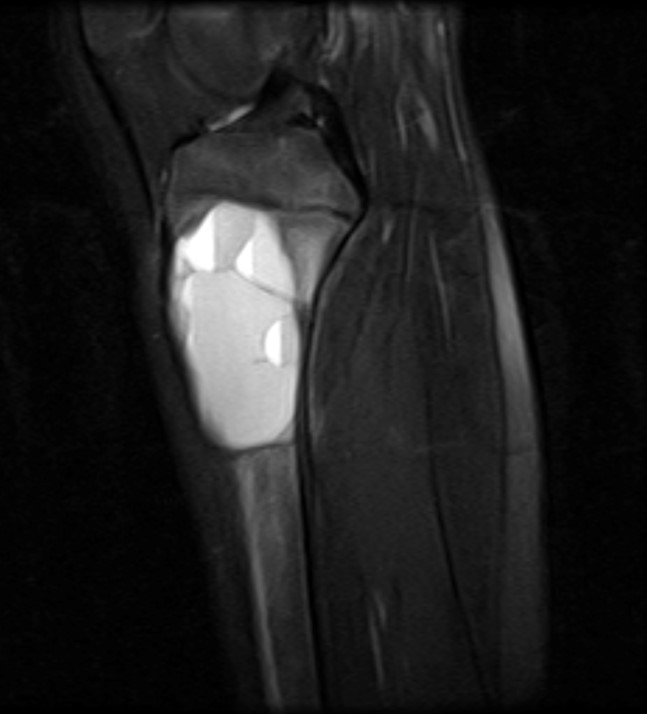

- Xray:

- Eccentric radiolucent lesion with expansile remodeling, involving the metaphysis of long bones

- Finger in the balloon sign possible (Orthop Traumatol Surg Res 2015;101:S119)

- MRI:

- Multiloculated cyst with characteristic fluid-fluid levels

Radiology images